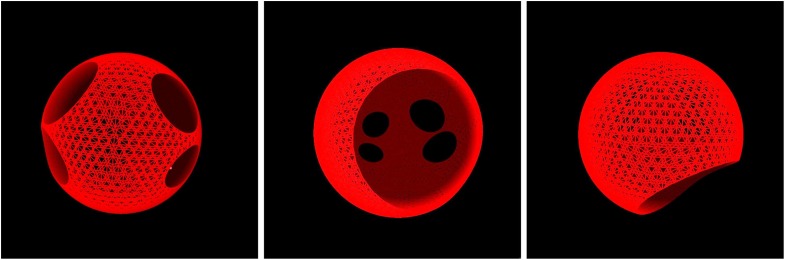

3D Sphere (340–5,680 nodes)

Stable 3D spiral wave dynamics and multidirectional propagation. Validates 3D behavior before anatomical complexity.

The digital twin successfully reproduced multiple clinically relevant arrhythmia mechanisms observed in patients. By adjusting conduction velocities and applying precisely timed ectopic events, we induced various forms of reentrant activity including micro-reentry, macro-reentry, and atrial flutter. These arrhythmias demonstrated self-sustaining propagation patterns consistent with clinical observations.

Arrhythmia Induction

We successfully induced left atrial flutter by slowing conduction velocity between pulmonary vein openings and triggering ectopic events at specific locations and times. Reentrant circuits and rotors emerged naturally, producing sustained activation patterns that resembled those seen in real patients.

Virtual Ablation

Simulated catheter ablation reliably terminated reentrant activity and restored organized conduction patterns. We successfully eliminated induced flutters using virtual ablations, allowing the system to return to normal rhythm. The model demonstrated effectiveness on both idealized and patient-specific atrial geometries.

- 3D Rotation & Zoom: Freely rotate and inspect geometry

- Node Coloring: Toggle Color coded contraction phases

- Draw Front Half: Render only near half for clarity